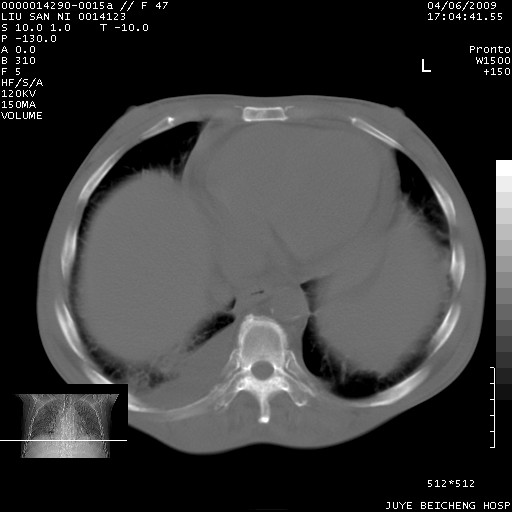

以下是引用前行在2009-4-7 10:31:00的发言:[br]肝脾肿大;双肾增大,双肾盂少量积水可能,肾膜膜增厚,肾周间隙增宽,并见桥间隔,提示结缔组系统疾病、系统性红瘢狼疮肾可能性大。继发右侧胸腔、心包、腹腔积液。